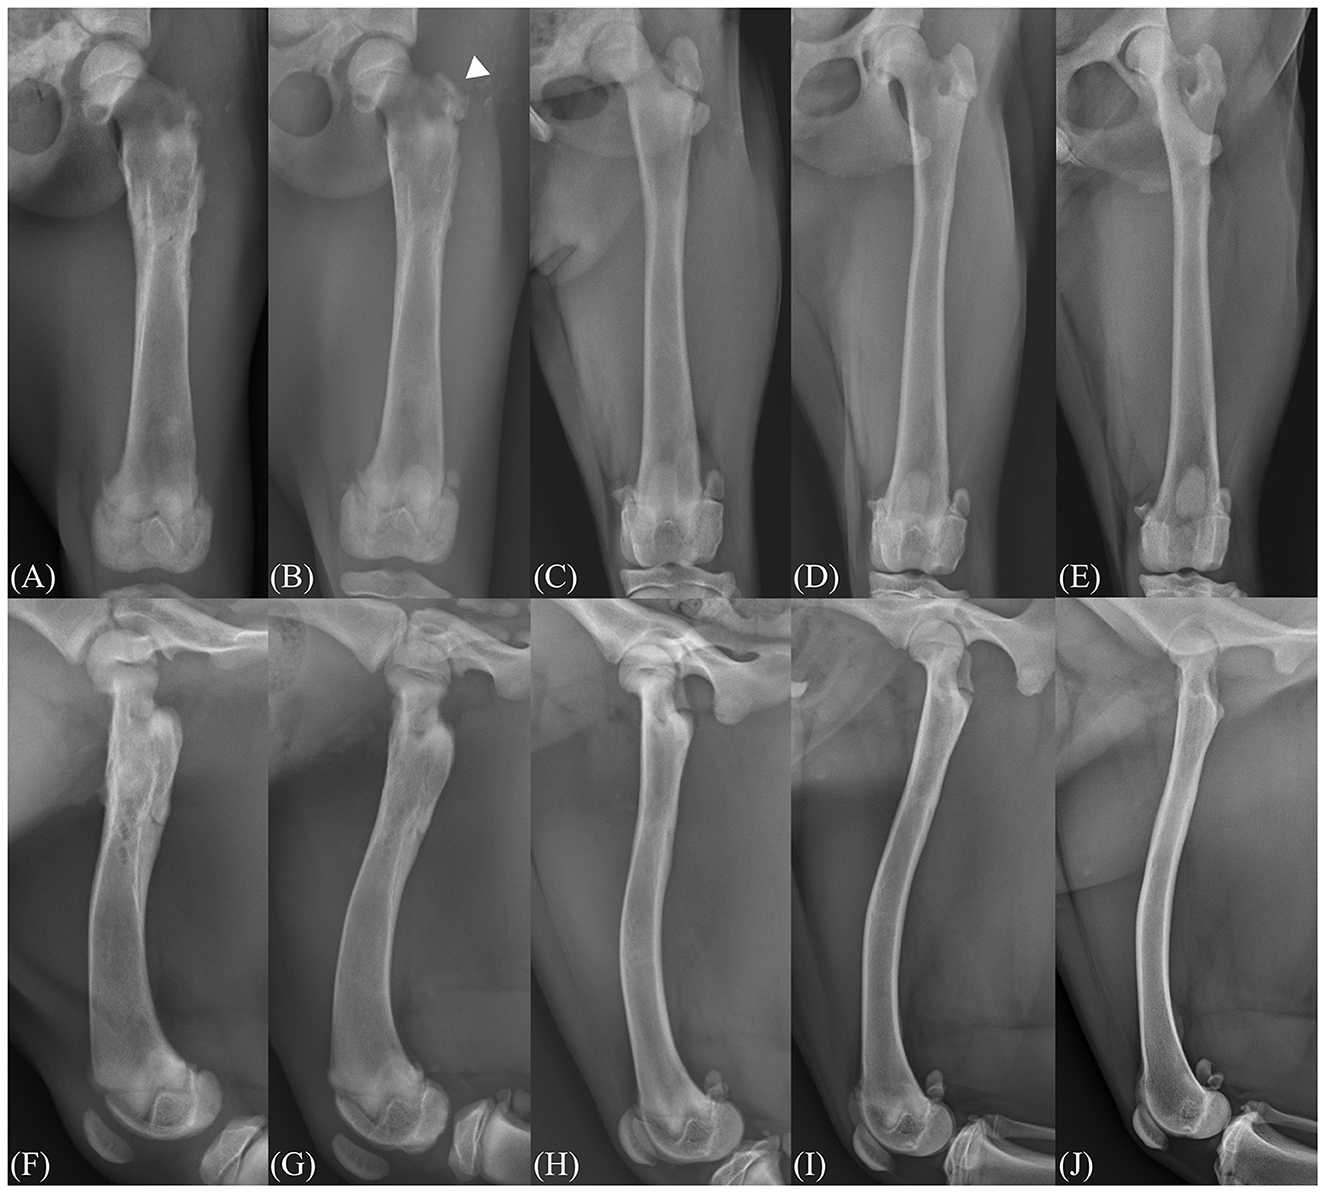

This case report describes the successful management of a subtrochanteric femoral fracture in a 2-month-old dog using temporary supratrochanteric plate fixation, performed prior to the development of the greater trochanter apophysis. A tibial plateau leveling osteotomy plate was applied to the proximolateral femur and subsequently removed following radiographic evidence of bridging callus formation. At the 21-month follow-up, the dog exhibited normal limb function, symmetrical femoral length, and appropriate development of the greater trochanter. Although a mild procurvatum deformity was noted, no clinical signs or range of motion deficits were observed. These findings support the use of temporary fixation across the trochanteric region as a feasible treatment strategy for immature subtrochanteric femoral fractures when performed prior to apophyseal development.